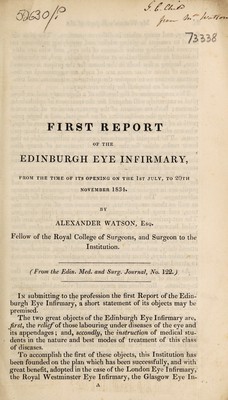

First report of the Edinburgh Eye Infirmary, from the time of its opening on the 1st July, to 20th November 1834 / [Alexander Watson].

- Watson, Alexander, 1799-1879

- Date:

- [1834]

Licence: Public Domain Mark

Credit: First report of the Edinburgh Eye Infirmary, from the time of its opening on the 1st July, to 20th November 1834 / [Alexander Watson]. Source: Wellcome Collection.

1/16